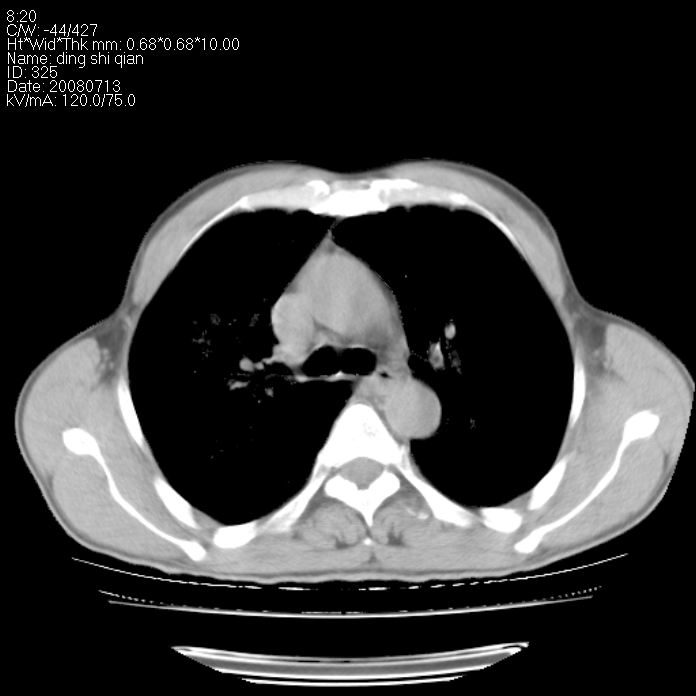

标题: CT14654:男 50岁 近来胸痛 [打印本页]

标题: CT14654:男 50岁 近来胸痛

右侧上肺块状软组织影,浅分叶,边缘毛刺证,与胸膜粘连,考虑:周围性肺癌

右肺上叶周围型肺癌可能性大。

右侧上肺块状软组织影,浅分叶,边缘毛刺证,与胸膜粘连,考虑:周围性肺癌!支持!

典型右肺周围型肺癌

首先考虑周围性肺癌,建议强化或穿刺明确

右肺上叶周围型肺癌。